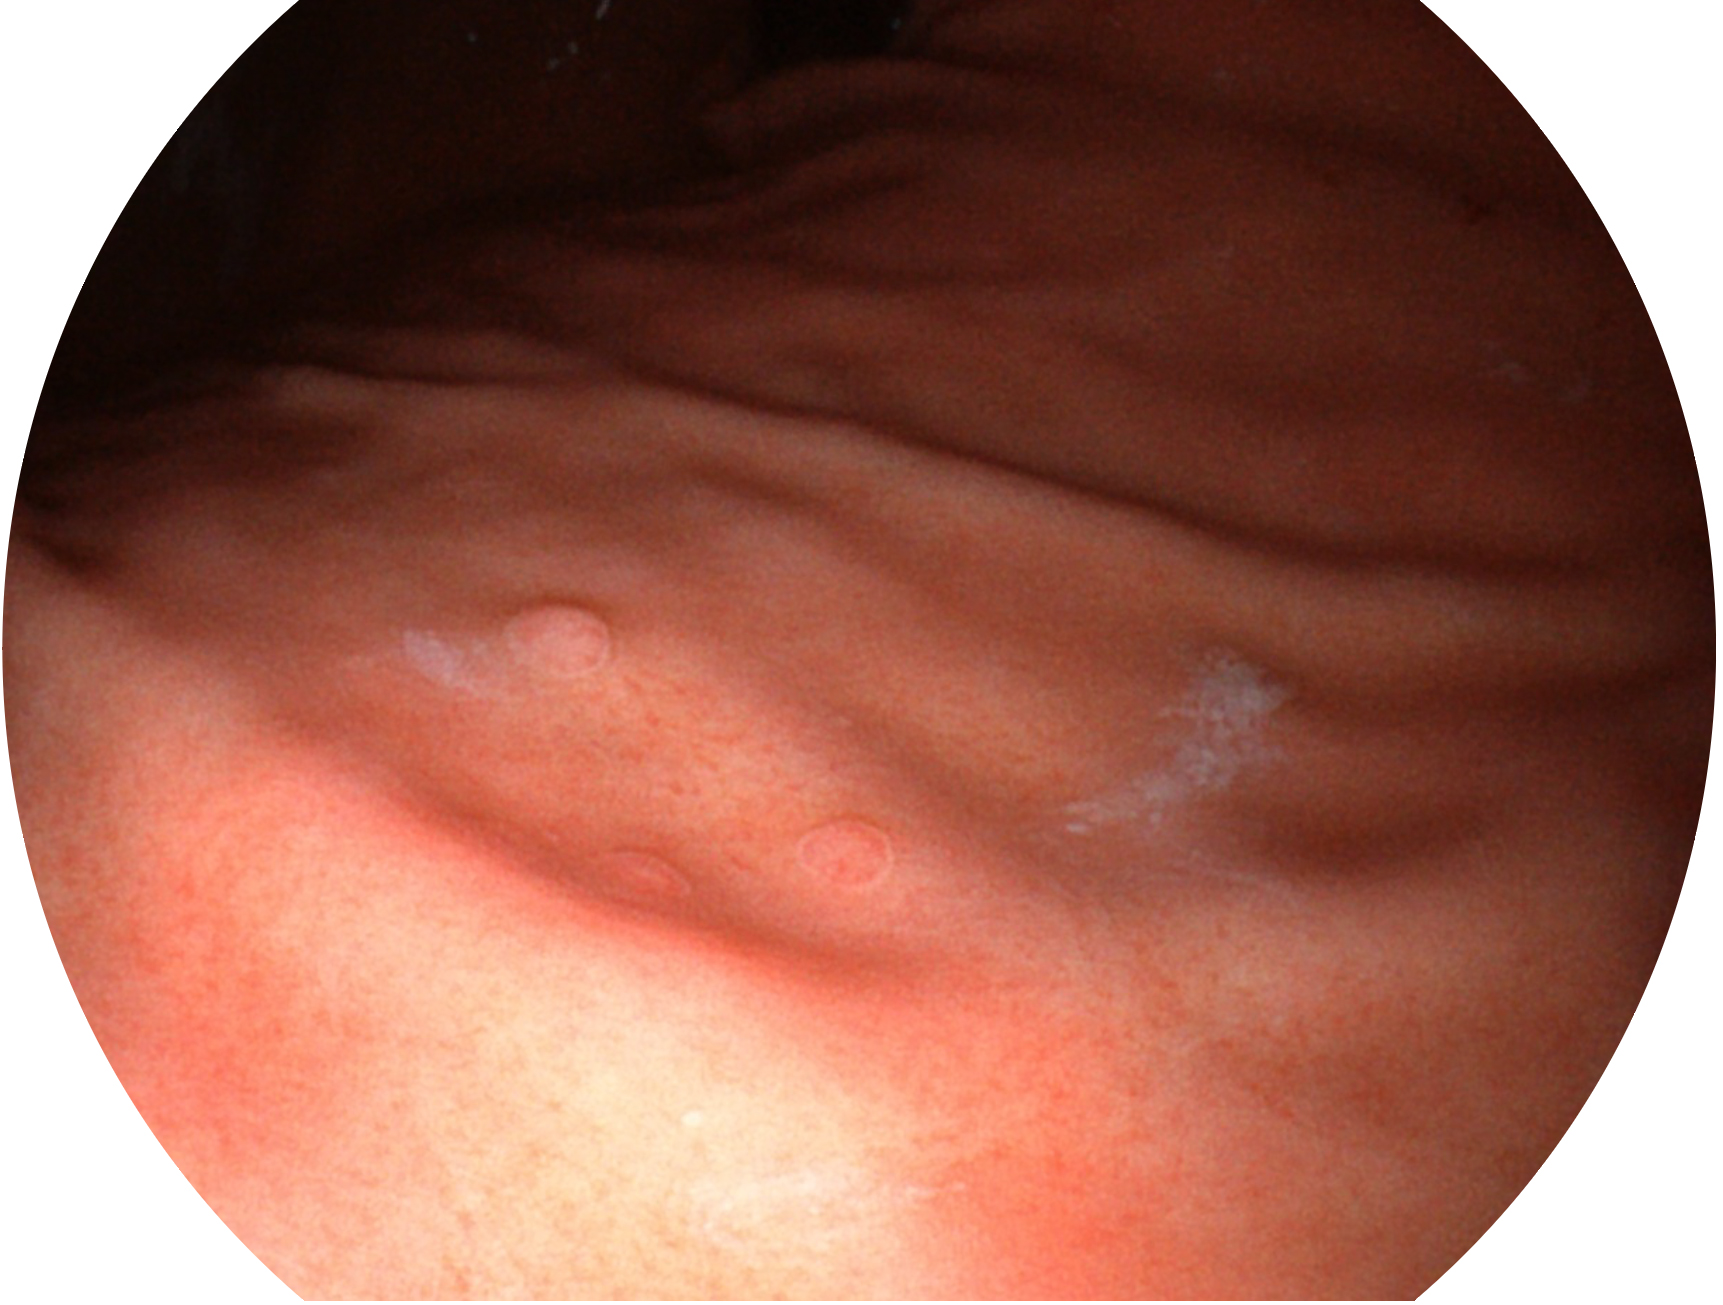

美狮贵宾会官网新开发的内镜染色技术,主要是基于多波长LED 光源的开发,VLS-55Q 四波长LED 光源是由四个不同颜色的LED光按照相应照明模式所规定的特定发光比例进行合束后形成,合束后形成的照明光的光谱由红光、绿光、蓝光及蓝紫光这四个不同的波段范围构成。具有更高光谱自由度,通过光谱比例的控制,实现了聚谱成像技术,英文全称为“Spectral Focused Imaging, SFI”,缩写为“SFI”和光电复合染色成像技术,英文全称为“Versatile Intelligent Staining Technology, VIST”,缩写为“VIST”。